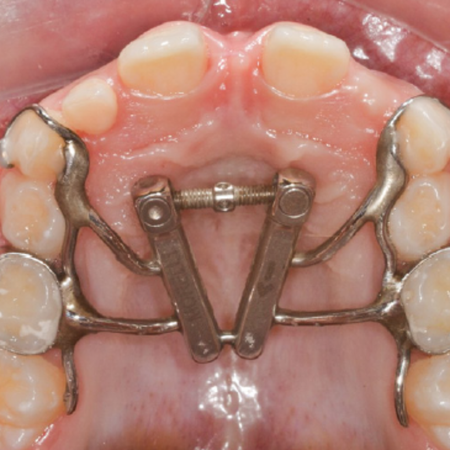

Abertura da sutura palatina mediana após expansão diferencial e em leque: análise secundária de um ensaio clínico randomizado

Objetivo: Comparar a abertura da sutura palatina mediana após a expansão rápida da maxila realizada com o expansor maxilar com abertura diferencial e com o expansor em leque. Métodos: Expansão rápida da maxila foi realizada com o expansor maxilar com abertura diferencial (n=12; 8 do sexo feminino, 4 do masculino; média de idade de 7,75 anos) e com o expansor em leque (n=12; 8 do sexo feminino, 4 do sexo masculino; média de idade de 8,08 anos). Tomografias computadorizadas de feixe...

Midpalatal suture split after differential and fan-type expansion: a secondary analysis from a randomized clinical trial

Objective: To compare the opening of the midpalatal suture after rapid maxillary expansion (RME) with the expander with differential opening and the fan-type expander. Methods: Rapid maxillary expansion was performed with the expander with differential opening (n=12, 8 female, 4 male, mean age of 7.75 years) and the fan-type expander (n=12, 8 female, 4 male, mean age 8.08 years). CBCT scans were acquired before (T1) and immediately after (T2) the expansion. The outcomes comprised the opening...